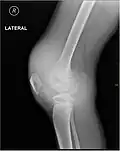

Radiographie montrant un début d'hémarthrose.